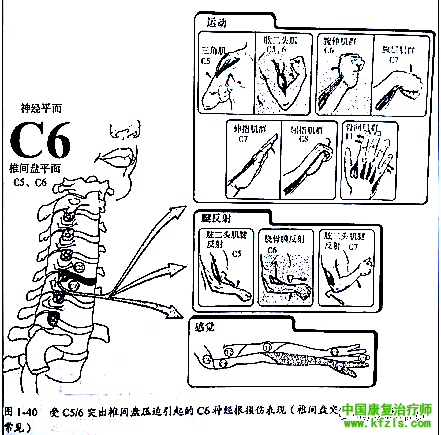

突出的椎间盘从上方压迫自椎间盘上方发出并行经椎旁椎间孔的神经根,并导致相应神经节段受累。如 C5和C6椎间盘突出将从上方压迫C6神经根(图1-33 )。

采用下述神经功能检査方法即可确定椎间盘突出的相应平面(图1-39至1-43)。

如创伤引起的C6神经根损伤可导致前臂外侧的感觉减退,伸腕肌肌无力和肱桡肌反射消失(图1-40)。但也可出现唯一症状:肩胛骨的内上角和内侧缘疼痛。